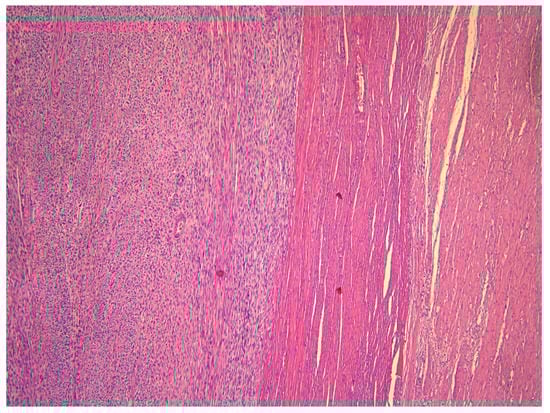

3. Anatomopathological Features

- smooth muscle tumors with focal/multifocal or diffuse cytological atypia (moderate-to-severe), lacking coagulative tumor necrosis and 6–9 mitoses per 10 HPFs (2–4 mitoses/mm2).

- Tumors that lack cytological atypia or raised mitotic count but having unequivocal coagulative tumor necrosis.

- Tumors with elevated mitotic count (>15 mitoses per 10 HPFs or >6 mitoses/mm2) but lacking coagulative tumor necrosis or cytological atypia.

- Tumors with uncertain mitotic count but having diffuse cytological atypia (moderate-to-severe).